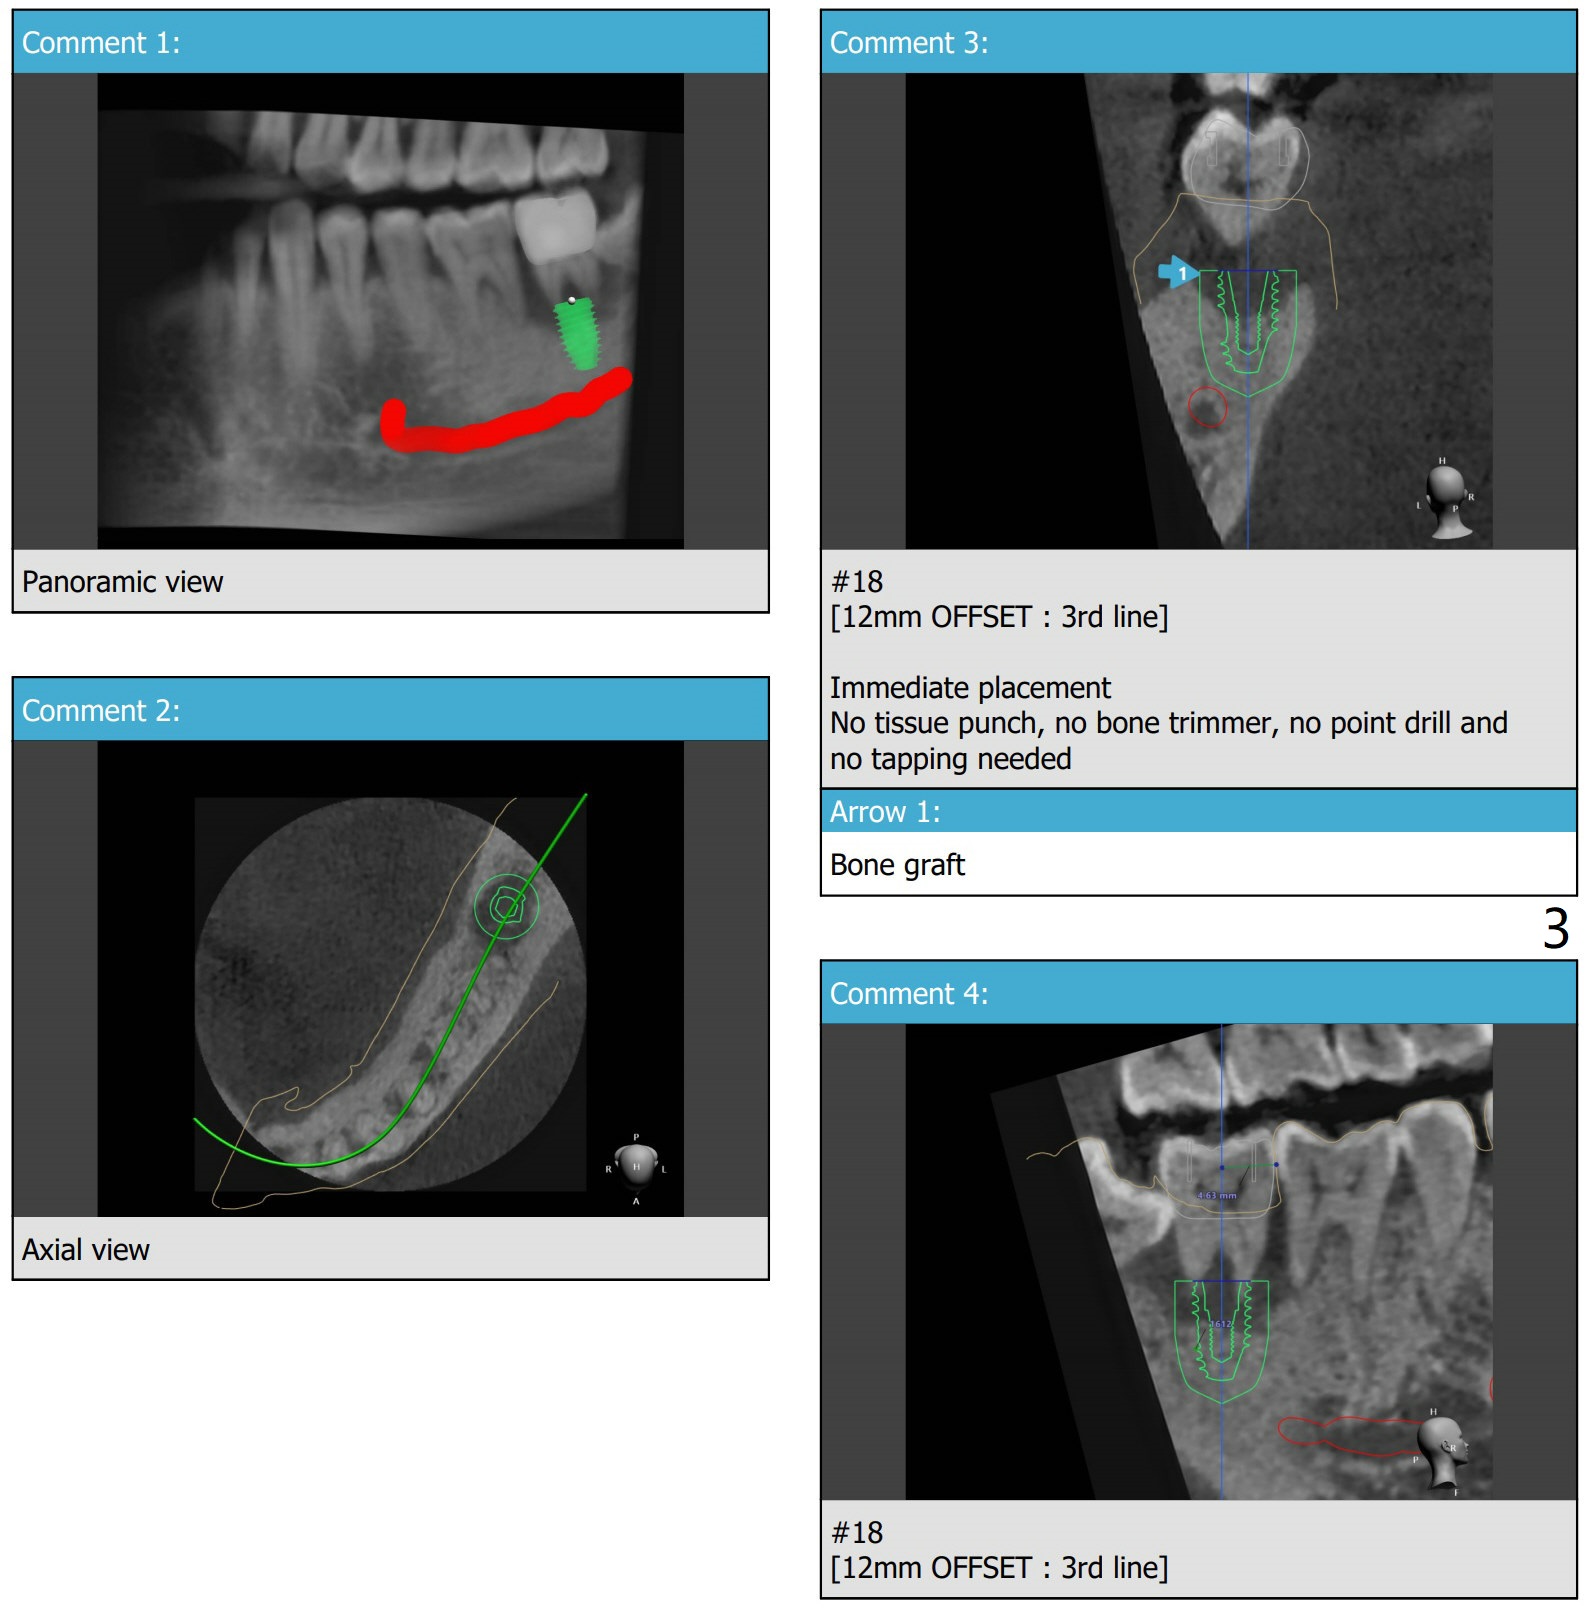

40岁男(吸烟一天1/2包)右下7植牙牙冠粘固后3个月回来要求拔除左下7松动牙(图一)。由于骨质吸收严重,植体短,不必种植牙槽窝近中斜面,植入后拔除8,填入胶原塞,7牙槽窝放置粘性骨粉,覆盖PRF膜后制作临时牙冠。FC 5x9。6远中洁治,涂Endogain,确保放置粘性骨粉,压迫,压紧。